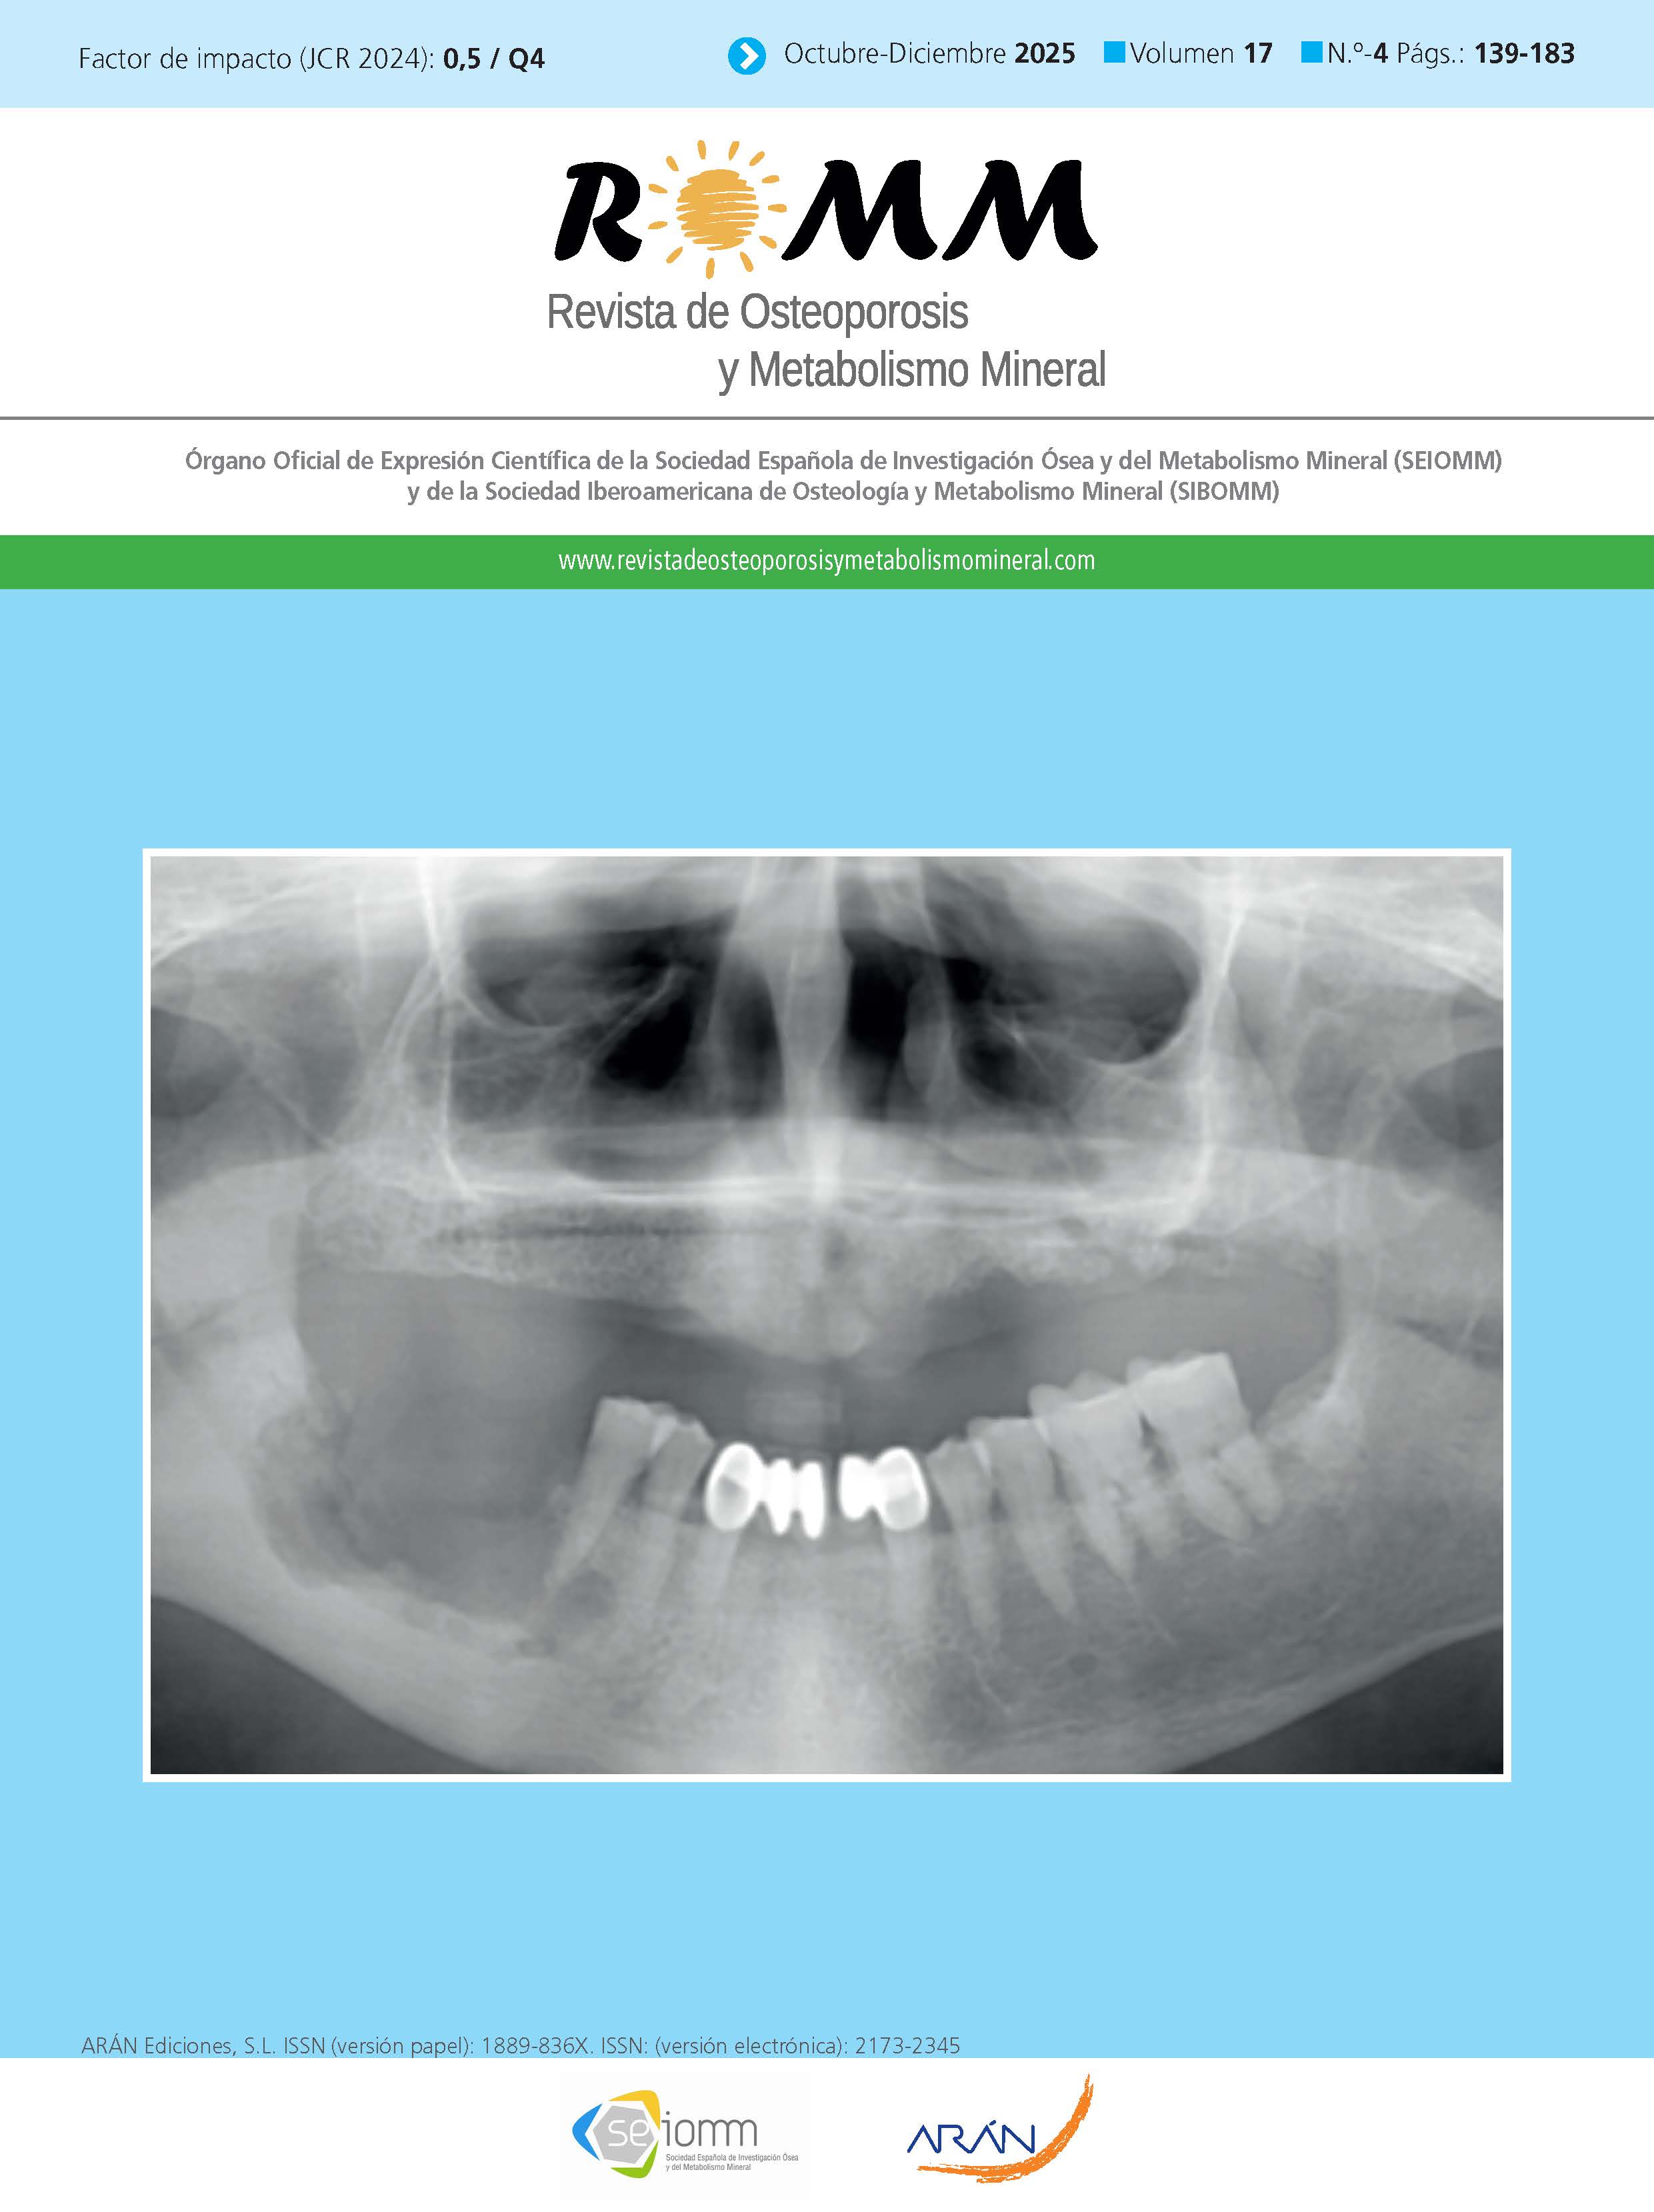

María Pilar Aguado Acín, Pedro Infante Cossío, José V. Bagán, José Nart, Luis Miguel Redondo González, Marta Zafra Poves, Carmen García Insausti, María Casanova Espinosa, José Luis Cebrián Carretero, Guillermo Martínez Diaz-Guerra